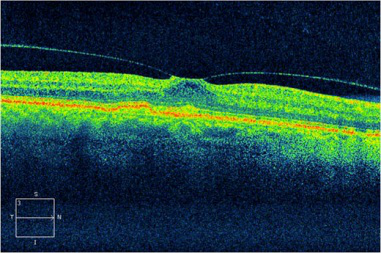

(OCT查验显示信息双眼的黄斑前膜,化学纤维膜在黄斑表层造成伸展的能量,可导致黄斑浮肿或孔裂,导致视线中间出現冷色)